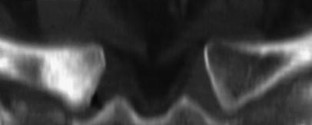

SAPHO: syndrome or concept? Imaging findings

The SAPHO syndrome was a term coined to include a variety of musculoskeletal disorders associated with skin conditions, mainly palmoplantar pustulosis and acne conglobata. It is more correctly a spectrum which includes the following: skin lesions, osteoarticular manifestations of synovitis hyperostosis and osteitis affecting particular target sites, and·a clinical course marked by relapses and remissions. The major sites of involvement are the anterior chest wall, the spine, long bones, flat bones, and large and small joints. The distribution and severity of involvement varies from the adult to the pediatric form of chronic recurrent multifocal osteomyelitis (CRMO). The diagnosis of SAPHO syndrome is not difficult when the typical osteoarticular lesions are located in characteristic target sites. The diagnosis is more difficult if atypical sites are involved and there is no skin disease.